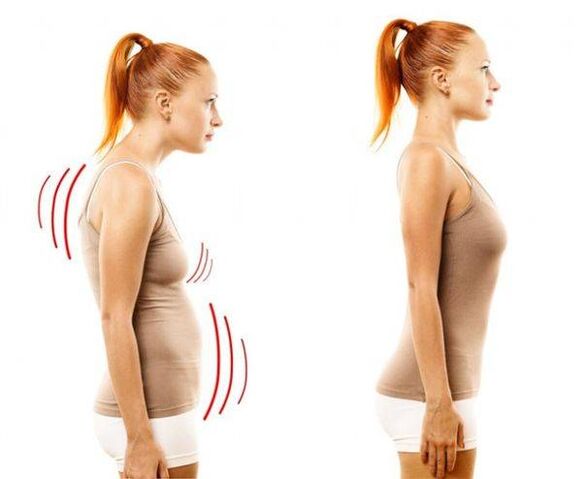

ဤရောဂါတွင်၊ ကျောရိုးချပ်ပြား၏ အူတိုင်သည် ပါးလွှာလာပြီး ခြောက်သွားကာ၊ ၎င်းအနီးတစ်ဝိုက်ရှိ အမျှင်တစ်ရှူးများ ယိုယွင်းလာကာ အရိုးနုတစ်သျှူးများသည် အပျက်သဘောဆောင်သော အပြောင်းအလဲများကို ကြုံတွေ့လာရသည်။ ကျောရိုးသည် သာမာန်ဝန်အားကို ထိန်းကျောင်းနိုင်ခြင်း မရှိတော့ဘဲ ပေါ်လာသည် - ၎င်းကို အစပိုင်းတွင် ယောင်ဝါးဝါးဖော်ပြသော်လည်း အချိန်ကြာလာသည်နှင့်အမျှ ပိုမိုပြင်းထန်လာကာ နာကျင်မှု၏အသွင်အပြင်တွင် အဓိကဖော်ပြသည်။ သို့သော်၊ သိသိသာသာစိတ်ဖိစီးမှု - အထိုင်များသောလူနေမှုပုံစံ၊ အထိုင်များသောအလုပ်၊ အဆက်မပြတ်စိတ်ဖိစီးမှု၊ ကိုယ်ဟန်အနေအထားညံ့ဖျင်းခြင်းနှင့်နောက်ကျောဒဏ်ရာ - များမကြာမီသို့မဟုတ်နောက်ပိုင်းတွင် osteochondrosis သည် thoracic ဒေသအပေါ်သက်ရောက်မှုရှိသည်။ ဤရောဂါသည် အလွန်အဖြစ်များသည်ဟု ယူဆသည် - တတိယအရွယ်ရောက်ပြီးသူတိုင်း ယင်းရောဂါကို ခံစားနေရသည်။